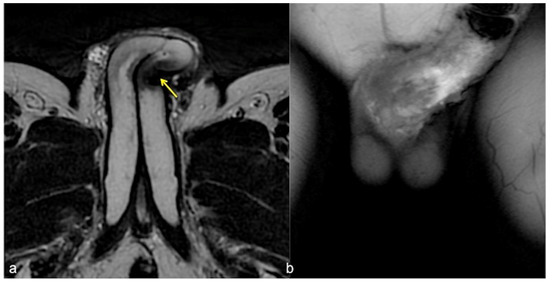

Figure 8.

Cav-MRI. GRE T1W 3D FS axial image displayed with MIP reconstruction shows an ineffective erection supported by superficial venous leakage mediated by the external pudendal veins (arrows).